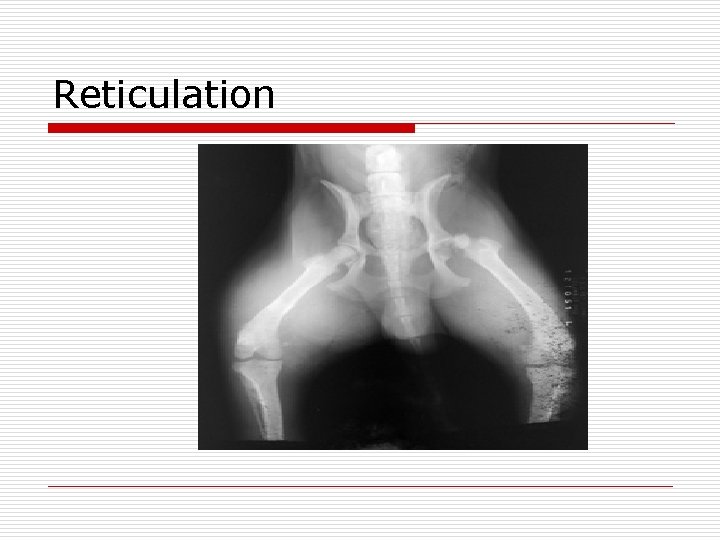

Chemicals o All chemicals should be kept at same temperature. o Variances in temperature between the chemicals can result in film reticulation. n Reticulation- a darkroom artifact produced by variable chemical temperatures that cause irregular expansion and contraction of the film emulsion, resulting in a mottled density appearance.

Reticulation